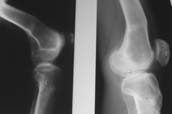

Пациент В. 53 лет, травма в феврале 2009. ДЗ. Открытый оскольчатый перелом нижней трети голени. При боли поступлении выполено ПХО, аппарат Илизарова. В последующем проводили ВХО, резекция костных отломков, укорочение 6 см, рана зажила. Была выполнена остеотомия большеберцовой кости в проксимальном отделе, резекция. Производилось тракция. На последних рентгенограммах выявлено, что одновременно с "выращиванием" регенерата произошло низведение надколенника на длину выращенного регенерата. Клинически: активное разгибание сохранено, объем движений в колене 180-110 градусов. Черными стрелками обозначен верхний край надколенника с одной и с другой стороны. Красная стрелка обозначает пальпируемую связку надколенника. Причина - остеотомия выше места прикрепления связки надколенника. Вопрос: была ли у кого подобная ситуация? Что делать? При первом обдумывании приходит решение: отсечение места прикрепления связки надколенника с костным блоком, перемещение на "правильное" место, укорочение сухожилия четырехглавой мышцы.

По-моему, надколенник низвелся на величину, гораздо меньшую удлинению.

Я бы уменьшил диастаз между фрагментами сантиметра на два. Судя по снимкам, регенерат это может позволить.

Приношу свои извинения если выражусь некорректно (как коллега я думаю поймете). В первую очередь допущена ошибка по линии остеотомии, правильно было бы произвести косую остеотомию (во фронтальной плоскости) т.е. верхушка линии остеотомии начинается из под бугристости можно направить сверху вниз или наоборот, тем самым избежали бы дистракционную транспозицию lig.patella. Во вторых следуеть начать пассивные и активные движения в коленном суставе чем быстрее и максимально восстановите движения (всего 70 град) тем больше шансов воостановить функцию (аппарат не будет мешат), дело в том, что по мере непроизвольного перемещения надколенника верхний заворот и капсула сустава тоже сворачивается, сморщивается, спаевается с окружащими тканями(неоднократно обнаруживал во время разъеденения спаек после подобных случаев), а у Вас прошло уже почти 6 мес. По х-ray не возможно разглядеть в зоне open-frac есть сращение?